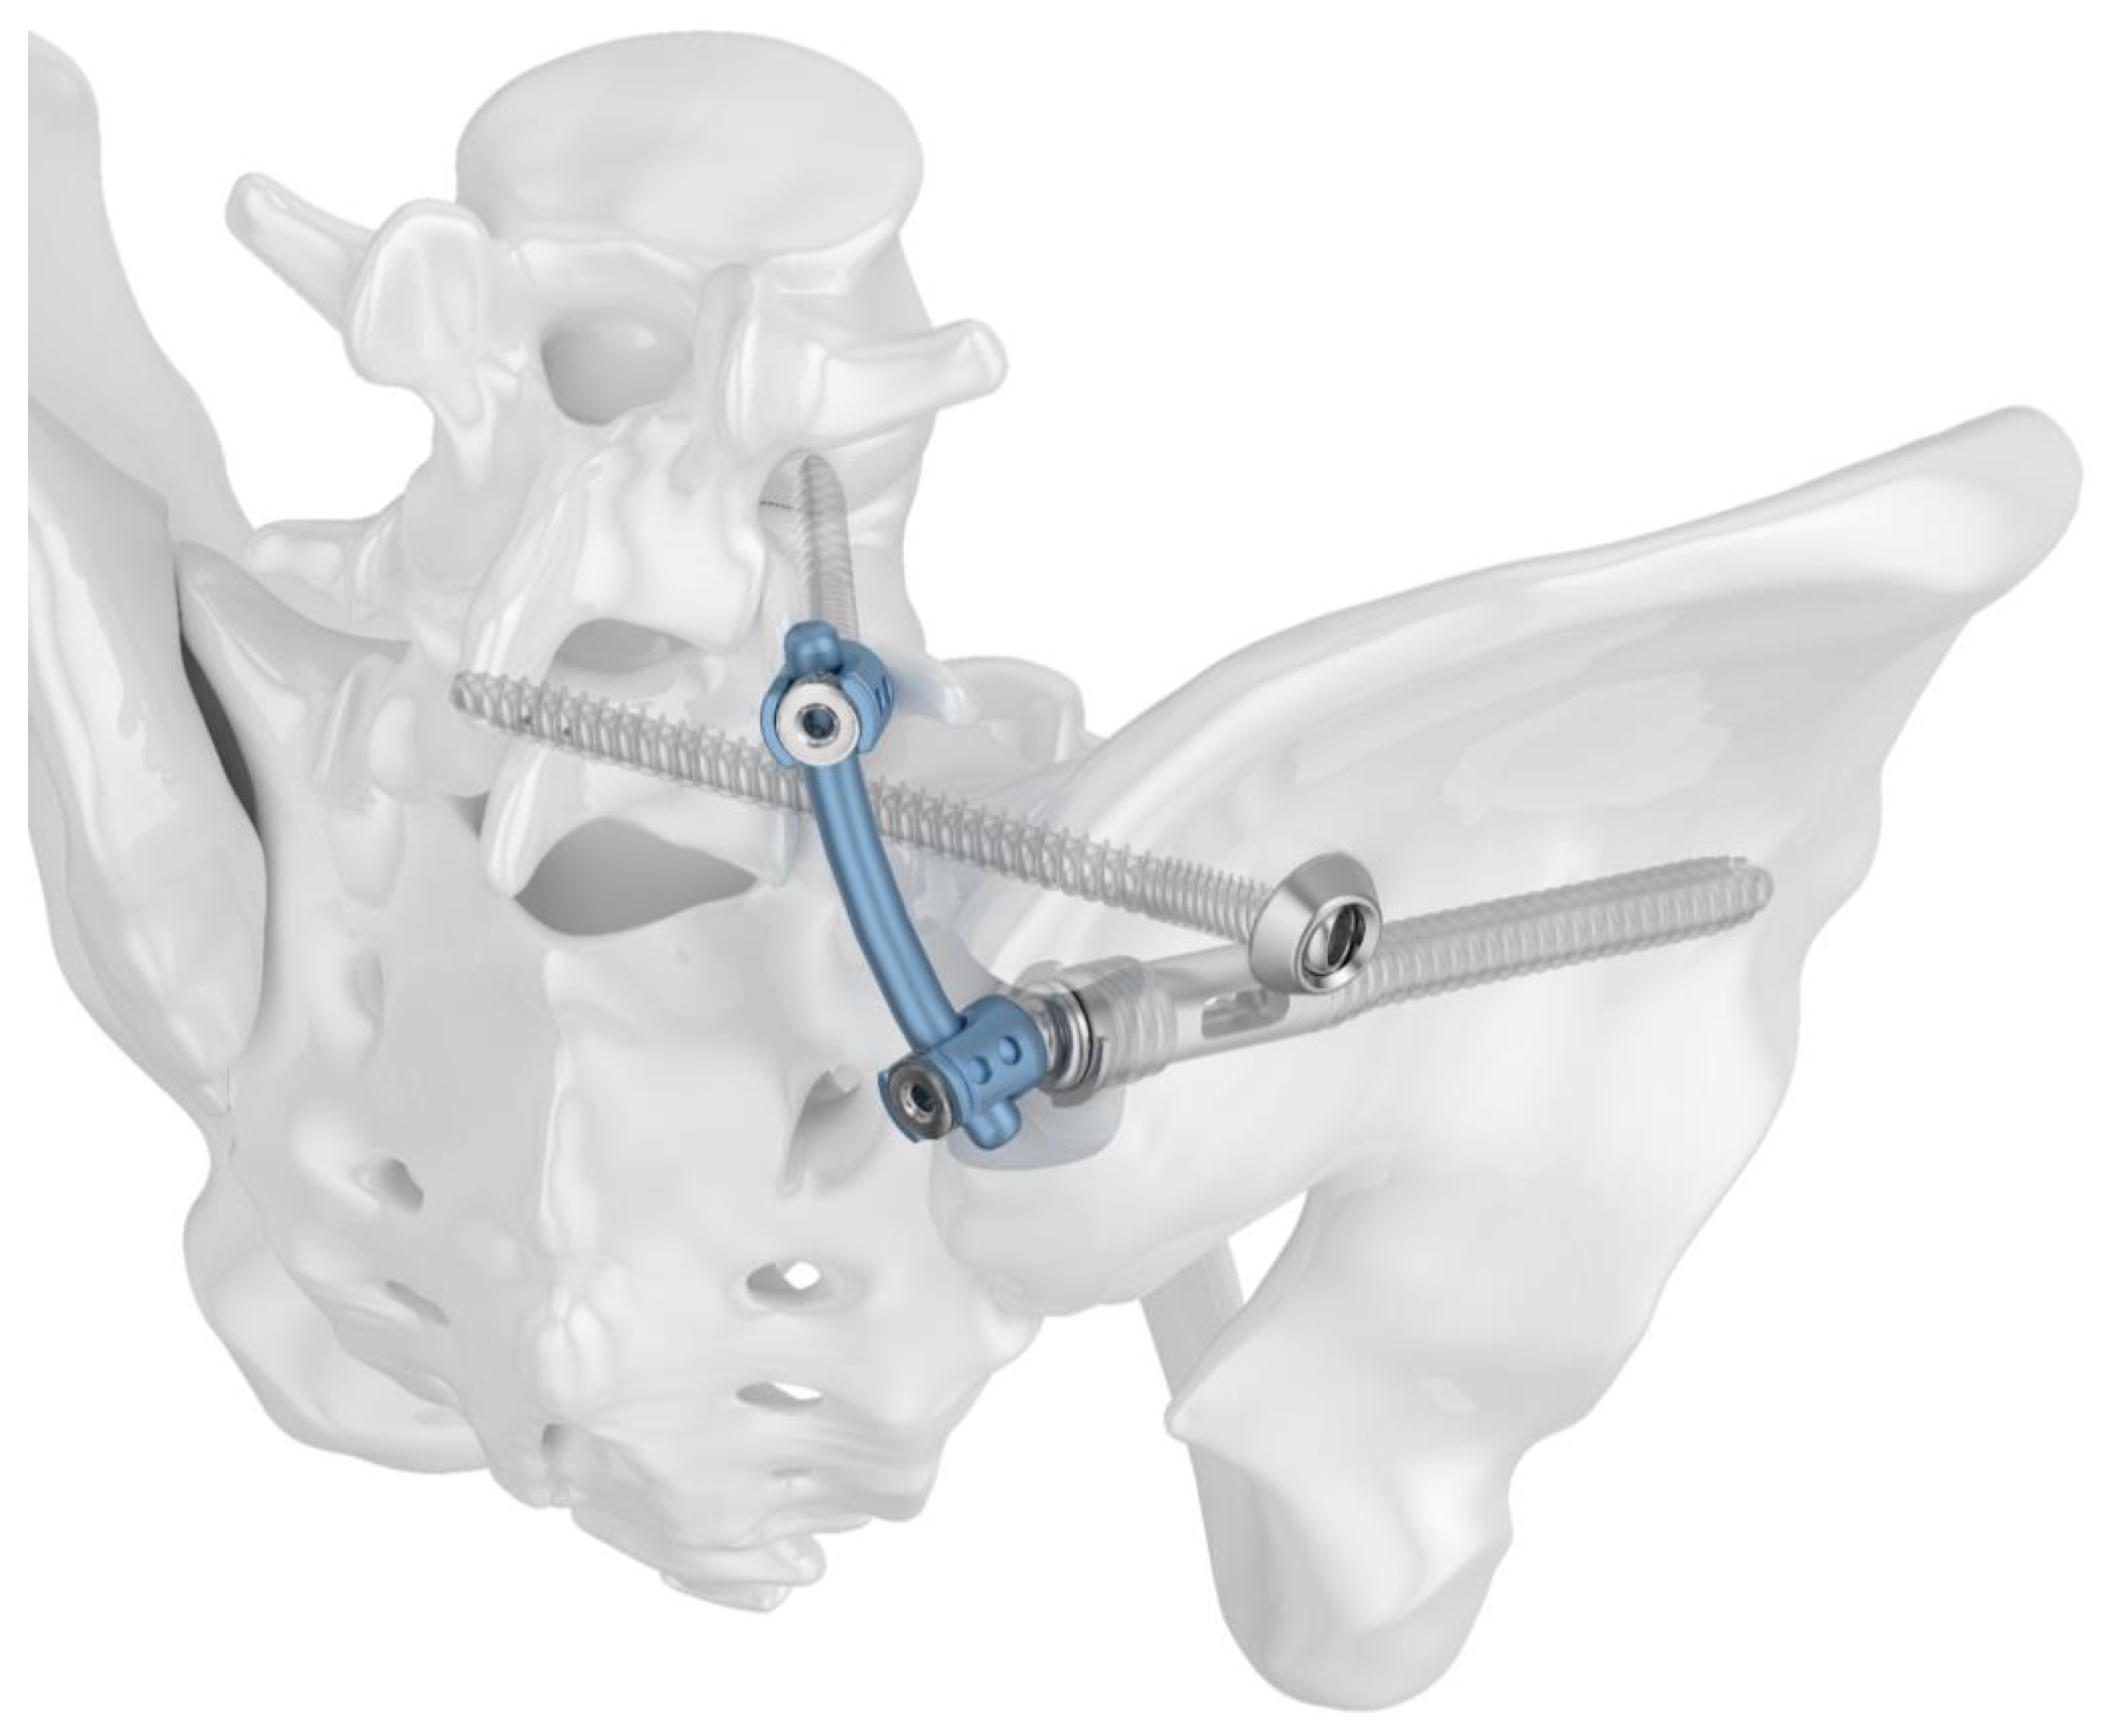

2.1. Implants

2.3. Fracture Model and Instrumentation